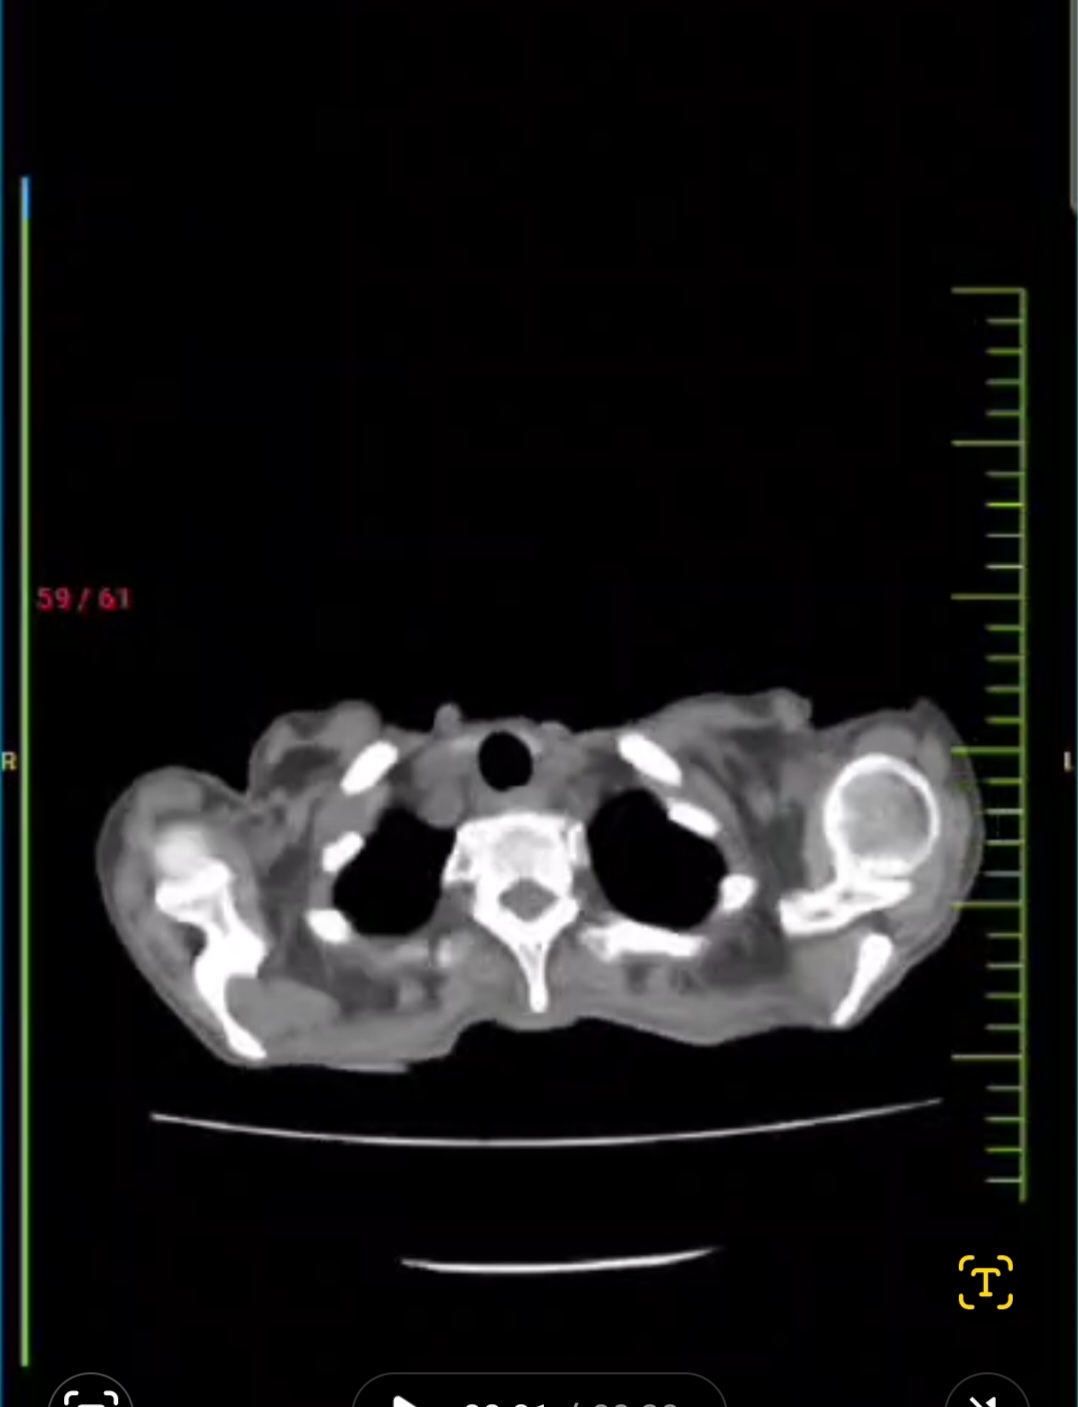

60F With Multiple lower lobe cavitation lesions with apparent pleural involvement.  Thanks for sharing this. Yes there's a possibility that she's loosing blood through her stools as a result of slow GI bleed. Can you share the image of the teeth? Since when was it noticed?